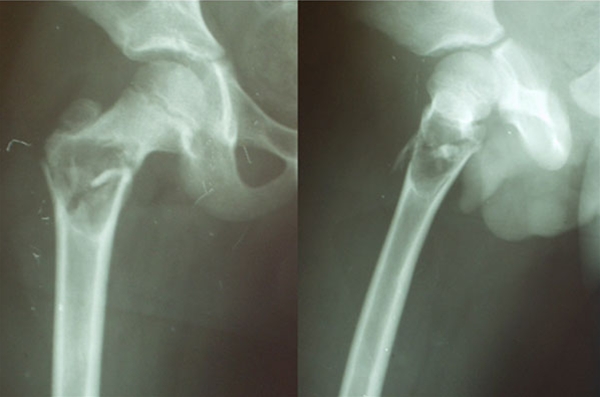

- Findes hyppigst som et bi-fund på røntgenbillede taget af anden årsag eller røntgen taget i forbindelse med patologisk fraktur

- Ved mistanke om malignitet kan suppleres med MR-skanning

- Kirurgisk behandling ved store cyster for at forhindre patologisk brud